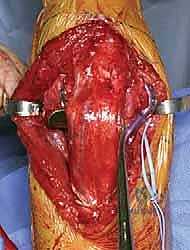

The immediate next step, prior to any deep dissection, is the identification, neurolysis, and protection of the ulnar nerve. The nerve is located proximally along the medial border of the triceps and traced distally into the cubital tunnel. The roof of the cubital tunnel (Osborne’s ligament) and the fascia of the flexor carpi ulnaris (FCU) are released to thoroughly decompress the nerve. Whether to perform a routine anterior subcutaneous transposition or leave the nerve in situ remains a topic of debate; however, if the hardware will impinge upon the nerve's native bed, or if extensive medial dissection is required, a tension-free anterior transposition using a fascial sling is highly recommended to prevent postoperative ulnar neuritis.

With the nerve protected, attention turns to the olecranon osteotomy. A chevron-shaped osteotomy, with the apex pointing distally, is preferred over a transverse cut as it provides inherent rotational stability and a larger surface area for healing. The osteotomy site is targeted at the bare area of the greater sigmoid notch, typically 2-3 centimeters distal to the olecranon tip. Crucially, before initiating the cut, the proximal ulna is pre-drilled and tapped for a 6.5mm or 7.3mm cannulated lag screw to ensure perfect alignment during subsequent repair. The osteotomy is initiated with a fine oscillating saw and completed with a thin osteotome to crack the subchondral bone, preserving the articular cartilage interdigitation. The olecranon fragment, with the triceps mechanism attached, is then reflected proximally, granting a breathtaking, 360-degree view of the distal humeral articular surface.

The fracture reduction sequence follows a strict "inside-out" and "bottom-up" philosophy. The primary objective is the anatomical restoration of the articular block (the "tie"). The trochlear and capitellar fragments are meticulously debrided of hematoma, reduced using pointed reduction forceps, and provisionally stabilized with smooth Kirschner wires. This articular assembly is then definitively fixed using headless compression screws or countersunk cortical lag screws, ensuring no hardware violates the joint surface. Once the articular block is reconstituted into a single, solid unit, it is reduced to the medial and lateral columns of the humeral diaphysis. Provisional fixation to the shaft is achieved with K-wires, and orthogonal fluoroscopy is utilized to confirm anatomical alignment, particularly the crucial 30-degree anterior tilt of the articular surface.